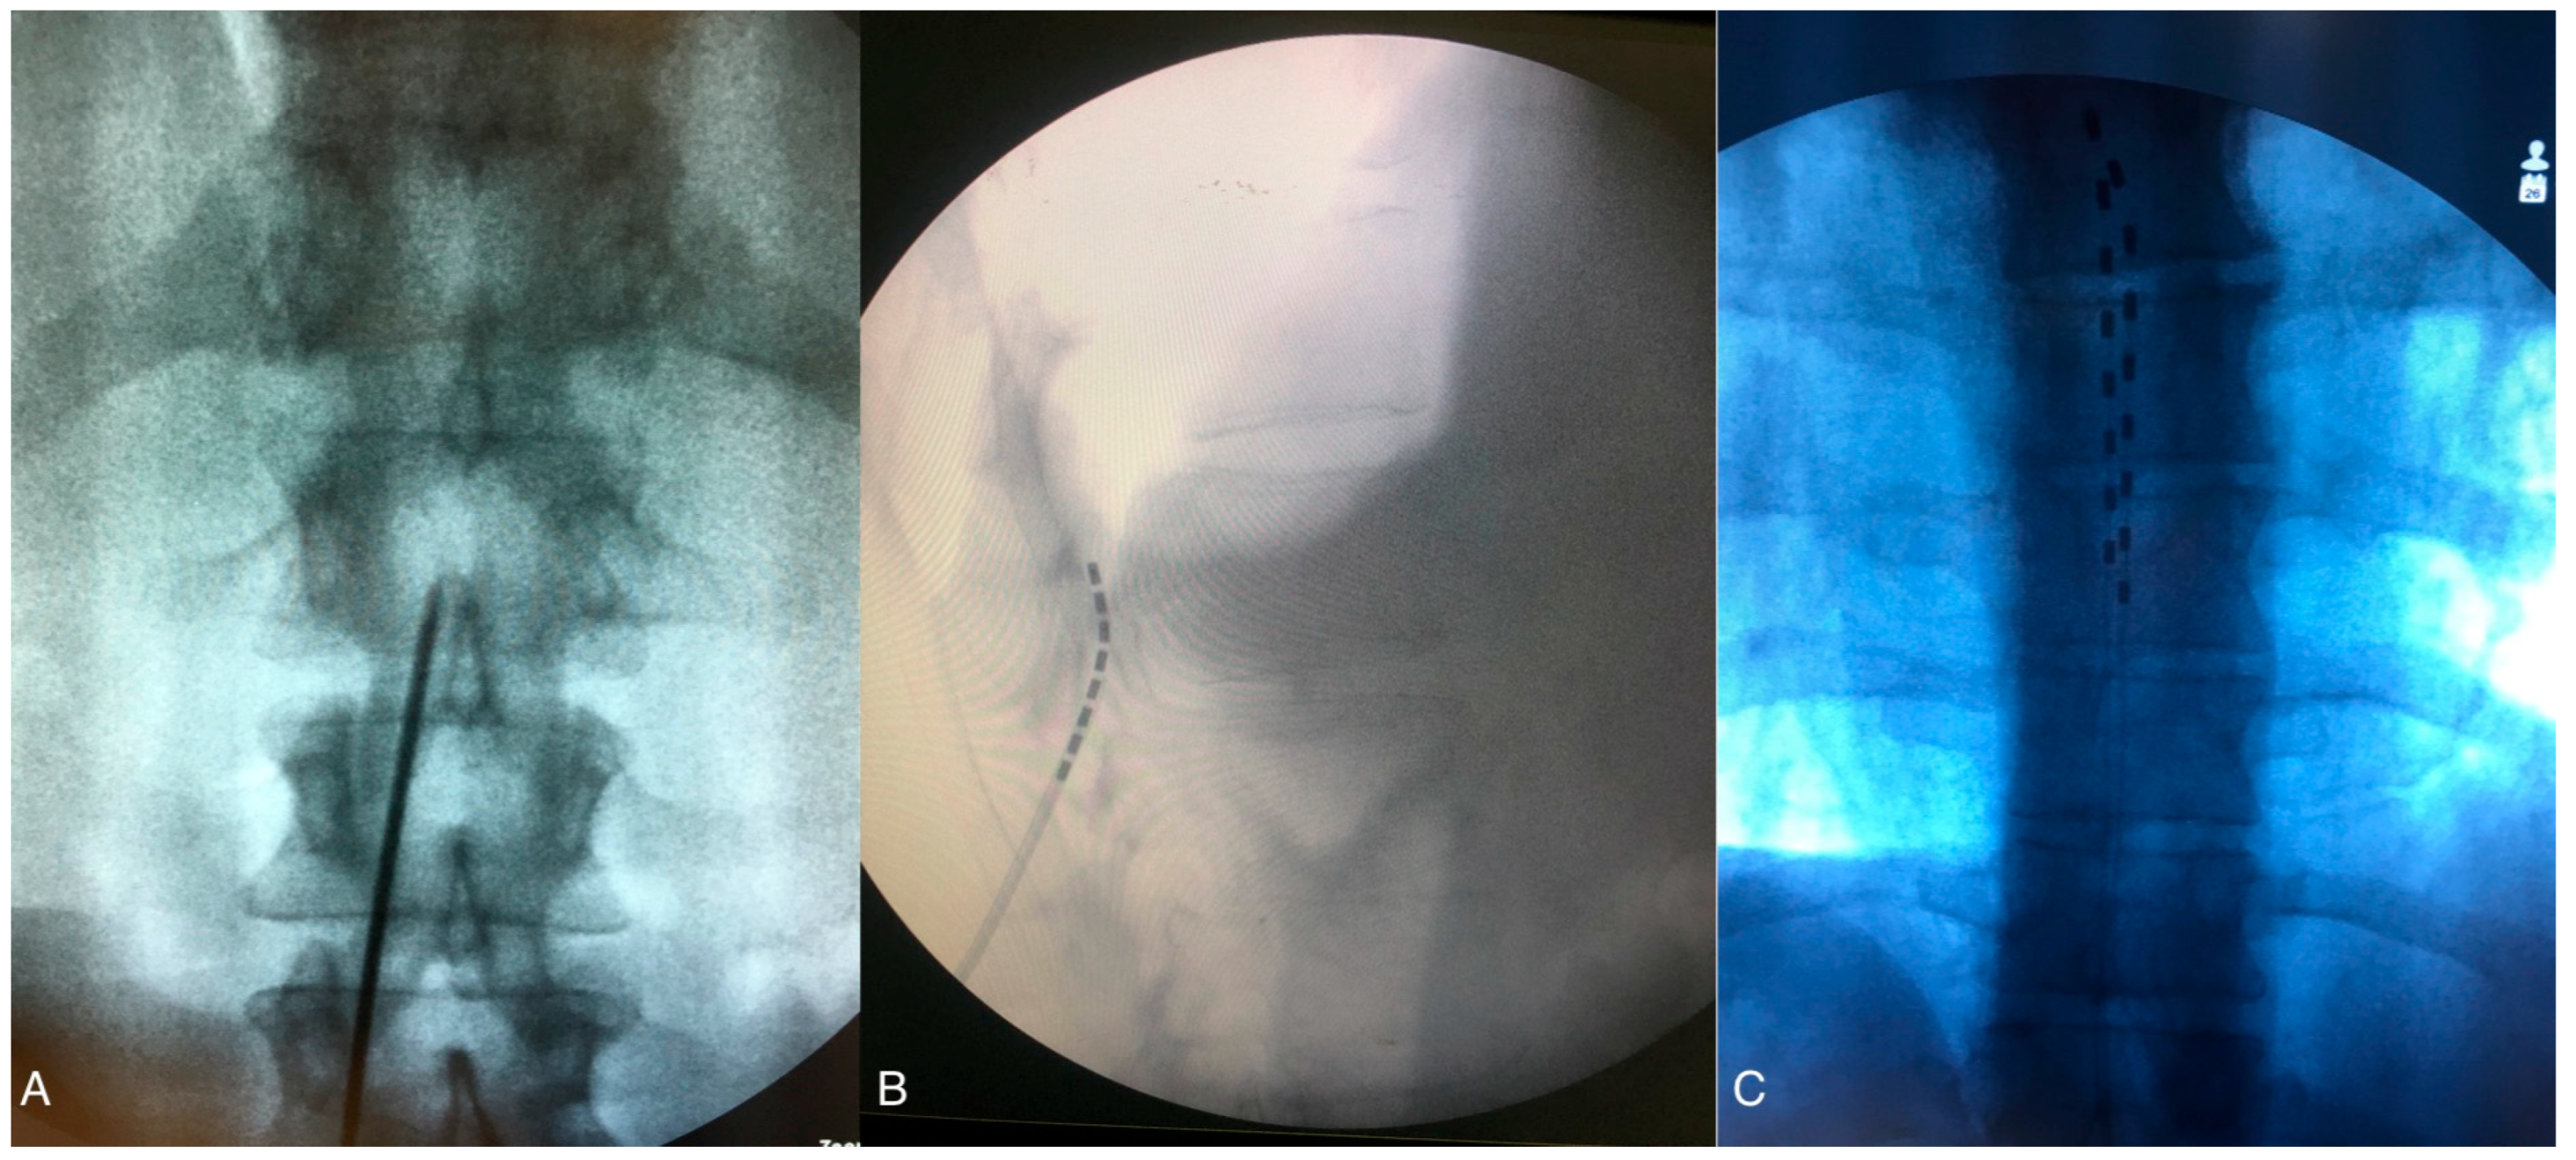

Generally, patients undergo two-phase process for SCS. The first phase, known as the Trial Phase, is conducted to determine the optimal location for the implanted electrodes and to assess the rate of pain relief and patient satisfaction during the trial period. Patients who respond well during this phase are considered good candidates for permanent SCS implantation. During the Trial Phase, the procedure is performed on lightly sedated patients. With the patient in the prone position, real time radiological control is utilized throughout the procedure. After skin and subcutaneous tissue local anesthesia, a linear incision is made down to the lumbar fascia, usually between L2 and L5. The Tuohy needle is then advanced under fluoroscopy through the fascia toward the interlaminar space until the tip engages the ligamentum flavum, allowing access to the epidural space (Figure 2A). A low-resistance syringe filled with air or with saline is attached to the needle, and gentle pressure is applied while advancing the needle. When the tip of the needle enters the epidural space, a loss of resistance confirms peridural entry. The electrode is then advanced through the needle under fluoroscopic guidance and moved upward in the epidural space to the appropriate level (usually T7–T9) (Figure 2B,C). Anterior–posterior and lateral fluoroscopic views ensure the dorsal placement of the lead, and intraoperative paresthesia mapping confirms coverage of the painful areas. With the advent of new waveforms modalities, such as high-frequency or differential target multiplexed (DTM) SCS, electrode placement can be guided by radiological findings to ensure accurate positioning at the correct spinal level (mid T8 vertebra to mid T10) without the need for paresthesia mapping [19], as detailed in Paragraph 1.5. Once the leads are in place, they are anchored to the lumbar fascia. Extension leads are then connected to an external pulse generator (EPG), and a sterile dressing is applied. In SCS trials, success for chronic pain patients is primarily defined by achieving at least a 50% reduction in perceived pain, whereas, for CLI patients, trial success encompasses not only significant pain relief but also improvements in limb perfusion, wound healing, and limb salvage, highlighting the broader therapeutic goals beyond mere pain reduction. A second surgical phase is then performed to implant a permanent SCS. Under local anesthesia, the lead extensions are removed, and the permanent leads are tunneled subcutaneously to the pocket where the battery, or internal pulse generator (IPG), will be placed. Typically, the permanent IPG is located in the uppermost quadrant of the gluteal region.

Figure 2. (A) Lumbar spinal X-ray, antero-posterior view: the Tuohy needle is advanced under fluoroscopy through the fascia toward the interlaminar space. (B) Fluoroscopic lateral view of the lumbar spine showing the tip of the needle entering the epidural space and being moved upward. (C) Antero–posterior fluoroscopic image of the two electrodes at T7 level. The figure was created by the authors.